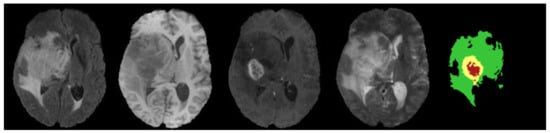

We evaluate our HMNet on three datasets [43,44,45]: (1) the BraTS 2018 dataset. It includes a training set of 285 samples and a validation set of 66 samples. (2) The BraTS 2019 dataset. It includes a training set of 335 samples and a validation set of 125 samples. (3) The BraTS 2020 dataset. It includes a training set of 369 samples and a validation set of 125 samples. Every sample in the training set includes four MRI modality images and a ground truth label, as shown in Figure 5. The size of the MRI images is 240 × 240 × 155 mm3, with the spacings among voxels are 1 × 1 × 1 mm3. The ground truth label includes enhancing tumors (label 4), peritumor edema (label 2), and necrotic and non-enhancing tumor cores (label 1). The validation results need to be uploaded to the online platform (https://ipp.cbica.upenn.edu/, accessed on 1 December 2022) for validation. The segmentation results can be divided into three classes: ET (label 1), WT (labels 1, 2 and 4), and TC (labels 1 and 4).

Figure 5. Visualization of a sample from the BraTS 2020 dataset. From left to right, there are Flair, T1, T1c and T2, respectively. The fifth image is the ground truth label. Label 1 is the necrotic and non-enhancing area in red. Label 2 is the edema area in green. Label 4 is the enhancing tumor area in yellow.